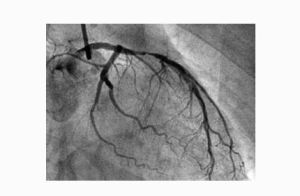

冠脈造影冠狀動脈造影是診斷冠心病的一種有效方法。將導管經大腿股動脈或其它周圍動脈插入,送至升主動脈,然後探尋左或右冠狀動脈口插入,注入造影劑,使冠狀動脈顯影。能較明確地揭示冠狀動脈的解剖畸形及其阻塞性病變的位置、程度與範圍。冠狀動脈造影是目前唯一能直接觀察冠狀動脈形態的論斷方法,醫學界號稱其為“金標準”。冠狀動脈造影術的死亡率約在0.11%-0.14%,心肌梗死率約在0%-0.06%;左冠狀動脈主幹病變患者的心肌梗死與死亡率均約在3.0%。